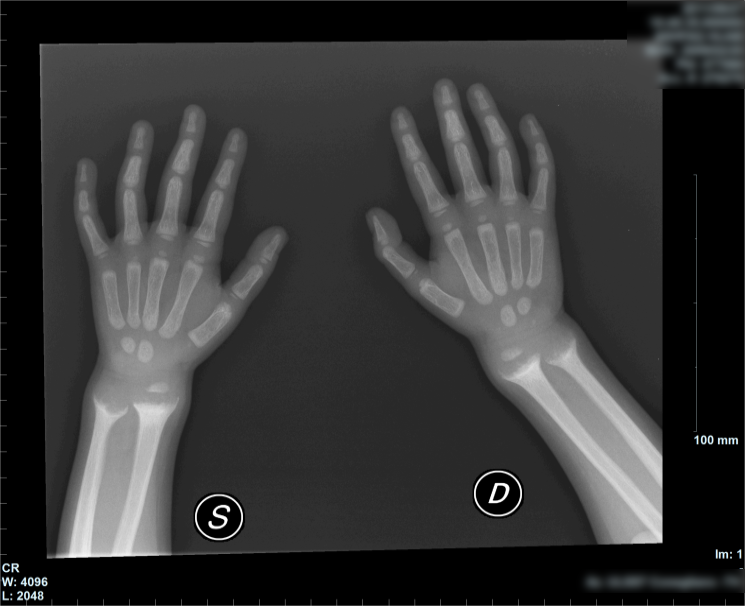

Agli esami ematici: Hb 10,2 g/dl, MCV 63 fL, EMA e TTG negativi, creatinina nella norma, AST 94 U/l, ALT 61 U/l, PT 1,8, PTT 1,57, D-dimero 963 ug/l, calcio plasmatico 9 mg /dl, calcio urinario < 1 mEq/l, fosfatemia 2,5 mg/dl, fosfato urinario 0,34 g/l, FA 530 ug/l, vit. D3 14,4 nmol/l, PTH 537 ng/l, proteine totali 5,4 g/dl, albumina 2,8 g/dl. Per l'ipertransaminasemia escludiamo cause infettive, autoimmuni, malattia di Wilson. Vengono inoltre escluse le principali cause di malassorbimento. ECG ed ecocardio risultano nella norma. Rx polso: �polsi e metafisi distali di radio e ulna allargate con deformazione a coppa�. Il quadro clinico, laboratoristico e radiologico consente di formalizzare la diagnosi di rachitismo carenziale (non eseguita profilassi con vitamina D) e avviare terapia con supplementazione di calcio (500 mg/die) e ergocalciferolo (vitamina D2) prima IM (300.000 UI in 3 somministrazioni) e successivamente per os (1000 UI).

La carenza di vitamina D rimane la causa pi� frequente di rachitismo sia per gli scarsi introiti che per l'inadeguata sintesi cutanea. I neonati maggiormente a rischio sono quelli allattati al seno, di etnia a pelle scura, malnutriti. Le manifestazioni cliniche comprendono: scarsa crescita, addome globoso, debolezza muscolare, fratture, craniotabe, ritardo della chiusura delle fontanelle e della dentizione, rosario rachitico, solco di Harrison, infezioni respiratorie, alterazioni del rachide (cifosi, scoliosi, lordosi), ingrossamento di polso e caviglia (braccialetto rachitico), deformit� in valgismo o in varismo, sintomi ipocalcemici (tetania, convulsioni, stridore). L'ipocalcemia � variabile e dipende dai livelli del PTH, l'ipofosfatemia � legata alla perdita renale PTH indotta, � presente ipocalciuria e iperfosfaturia, il PTH e la FA sono elevati, la 25(OH) vitamina D � ridotta. All'Rx � caratteristico l'allargamento dell'estremit� distale delle metafisi e la deformazione �a coppa�. La terapia si basa sulla somministrazione di vitamina D2 secondo due modalit�: la prima prevede una dose di attacco di 100.000-600.000 UI per os o IM in 1-5 giorni, seguita da una dose di mantenimento di 400-1000 UI/die; la seconda, una terapia giornaliera di 1000-10.000 UI/die per 8-12 settimane, seguite da un mantenimento di 400-1000 UI/die, garantendo inoltre la supplementazione dietetica (ed eventuale terapia per os) di calcio (30-75 mg/kg/die) e fosfato1.